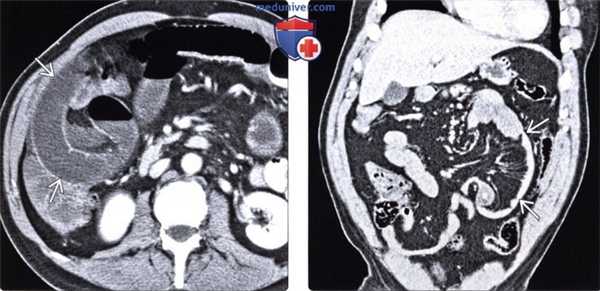

(Слева) На графическом изображении среза в аксиальной плоскости проиллюстрирована растянутая петля тонкой кишки, выбухающая в дефект брыжейки. Обратите внимание на периферическое положение тонкой кишки, смещение кнутри ободочной кишки, а также смещение брыжеечных сосудов.

(Справа) На аксиальной КГ с контрастным усилением у пациента после резекции ободочной кишки, выполненной ранее, визуализируется группа расширенных петель тонкой кишки в левой половине брюшной полости с передней стороны от поперечной ободочной кишки, а также брыжеечные сосуды, деформированные и переполненные кровью. Эти изменения являются типичными для чрезбрыжеечной грыжи. (Слева) На аксиальной КТ с контрастом у пациента с хирургическим вмешательством на органах брюшной полости в анамнезе визуализируются множественные растянутые, заполненные калом петли тонкой кишки В -проявление тонкокишечной обструкции.

(Справа) На корональной КТ с контрастным усилением у этого же пациента определяется, что эти петли В сгруппированы в боковых отделах живота, непосредственно примыкают к брюшной стенке и смещают ободочную кишку. Эти признаки в совокупности являются типичными для послеоперационной чрезбрыжеечной грыжи.

(Слева) На аксиальной КТ с контрастом определяется группа расширенных петель тонкой кишки, лежащих снаружи от смещенной ободочной кишки. Определяется также умеренно выраженный, не распространенный асцит, визуализируются полнокровные сосуды, что типично для грыжи брыжейки.

(Справа) На корональной КТ с контрастным усилением у пациента после панкреатодуоденэктомии (операции Уиппла) визуализируется тощая кишка, расположенная нетипично — напротив брюшной стенки. Стенка тощей кишки утолщена, брыжеечные сосуды полнокровны; определяется также небольшой асцит. В этом случае послеоперационная грыжа брыжейки послужила причиной ишемии кишки.